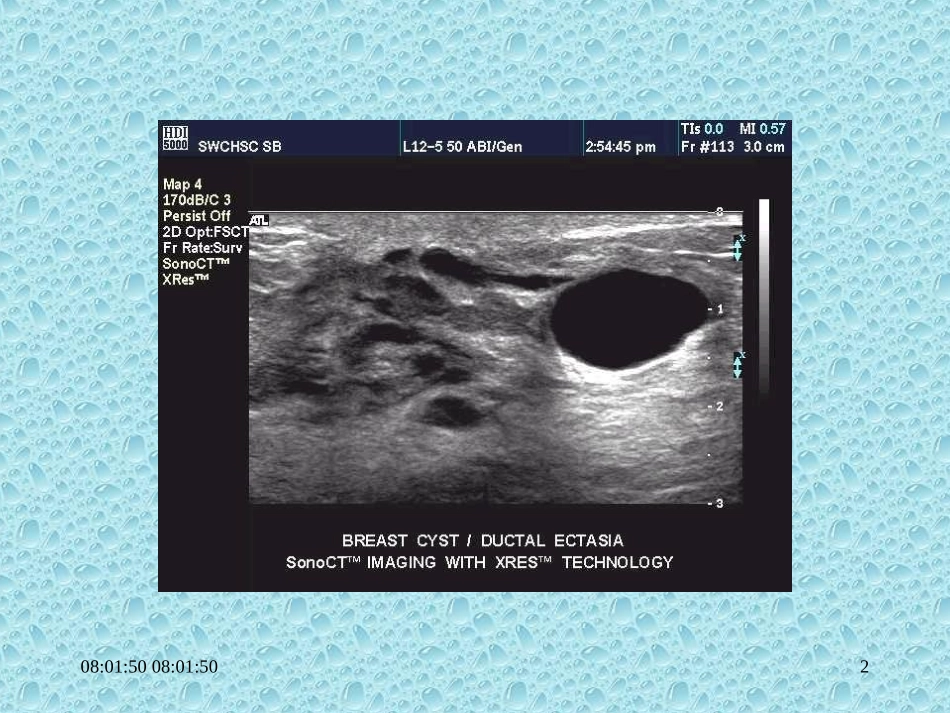

08:01:5008:01:501乳腺囊肿乳腺囊肿1.边界光滑、清楚,多指单纯性囊肿.2.内部呈无回声.3.后方回声增强,呈蝌蚪尾征.4.常为多发性,双侧存在.08:01:5008:01:50208:01:5008:01:50308:01:5008:01:50408:01:5008:01:505乳腺炎乳腺炎1.肿物边界模糊,增厚,回声增强.肿物边界模糊,增厚,回声增强.2.内部呈中强回声,分布不均.2.内部呈中强回声,分布不均.3.脓肿形成时,内部呈无回声区,边3.脓肿形成时,内部呈无回声区,边界增厚.界增厚.4.慢性炎症或液化不全,呈不均质点4.慢性炎症或液化不全,呈不均质点状及团块状回声.状及团块状回声.5.CDFI显示局部及周围血流信号5.CDFI显示局部及周围血流信号增多.增多.08:01:5008:01:506BreastAbscess08:01:5008:01:507右乳脓肿08:01:5008:01:508左乳脓肿右图为二维超声,左图灰阶血流显像图08:01:5008:01:509导管扩张症导管扩张症1.腺体内导管扩张呈低回声管状结构.2.导管内如有实性组织,则形成混合性肿块,后方不增强.3.CDFI呈供血丰富,轻中度,血流位于病灶中心区.08:01:5008:01:501008:01:5008:01:501108:01:5008:01:501208:01:5008:01:5013导管内乳头状瘤导管内乳头状瘤1.乳头内导管扩张,内有实性肿物,即有囊、有瘤呈囊实性改变.2.对不典型者,应挤压乳头,将分泌物涂片检查.08:01:5008:01:5014导管内乳头状瘤08:01:5008:01:501508:01:5008:01:5016导管乳头状瘤;示实性回声的血流显示08:01:5008:01:5017导管乳头状瘤,示导管的扩张及管内实性回声08:01:5008:01:5018乳房内异物乳房内异物1.有弹片伤或有乳房整形,再造求史.2.呈不规则低回声衰减暗区.3.植入硅胶囊者,可显示腺体与胸大肌之间,有一囊性硅胶填充物.08:01:5008:01:5019乳腺后异物——隆胸术后08:01:5008:01:5020乳腺后异物——隆胸术后08:01:5108:01:5121乳腺癌临床表现•临床表现:早期无痛性肿块——增大,肿块皮肤出现凹陷,橘子皮样改变,乳头凹陷。•转移腋下淋巴结——晚期,血行转移。08:01:5108:01:5122乳腺癌超声表现•肿块边界不清、不整,呈蟹足或锯齿样。•肿块内部呈低回声,回声不均。•癌瘤向前后方浸润,纵径大于横径,即纵横之比大于1。肿块向周围组织呈蟹足样浸润。•肿块中间液化坏死,出现不均质低回声或无回声。•后方回声衰减。•CDFI见血流较丰富,不规则,阻力指数高。•可转移至腋下淋巴结。08:01:5108:01:5123乳腺癌08:01:5108:01:5124乳腺癌乳腺癌乳腺癌乳腺癌08:01:5108:01:5125乳腺癌乳腺癌乳腺癌乳腺癌08:01:5108:01:5126乳腺癌乳腺癌乳腺癌乳腺癌08:01:5108:01:5127乳腺癌乳腺癌乳腺癌乳腺癌08:01:5108:01:5128乳腺癌乳腺癌乳腺癌乳腺癌08:01:5108:01:512908:01:5108:01:513008:01:5108:01:513108:01:5108:01:513208:01:5108:01:513308:01:5108:01:513408:01:5108:01:5135再复习一下良恶性肿瘤的鉴别要点吧08:01:5108:01:5136边缘及轮廓整齐、光滑不整、粗糙侧方声影有罕见包膜有无纵横比<1>108:01:5108:01:5137后壁回声整齐、增强不整、减弱肿物后回声正常或增强多有衰减皮肤浸润无可有组织湿润无可有内部回声均匀分布不均08:01:5108:01:5138钙化斑可有,较大微小微钙化对乳腺癌诊断的敏感性为35.29%,特异性为94.23%08:01:5108:01:5139彩色血流信号无或少丰富08:01:5108:01:5140乳腺超声的研究方向•新仪器及新技术的应用•乳癌的早期诊断•小乳癌的诊断•乳腺良、恶性病变的鉴别08:01:5108:01:5141乳腺超声的研究方向•超声诊断的病理学基础•超声、核素、CT、X线及热像图等比较•超声引导乳腺肿块抽吸、活检•术前定位08:01:5108:01:5142思考题思考题•乳腺癌的临床及超声表乳腺癌的临床及超声表现。现。•乳腺良性及恶性肿瘤的乳腺良性及恶性肿瘤的超声表现的鉴别要点。超声表现的鉴别要点。08:01:5108:01:5143参考书参考书•《浅表器官及组织超声诊断学》《浅表器官及组织超声诊断学》主编:张缙熙姜育新主编:张缙熙姜育新•《超声医学》《超声医学》主编:郭万学周永昌主编:郭万学周永昌08:01:5108:01:5144欢迎同学们来超声科实习